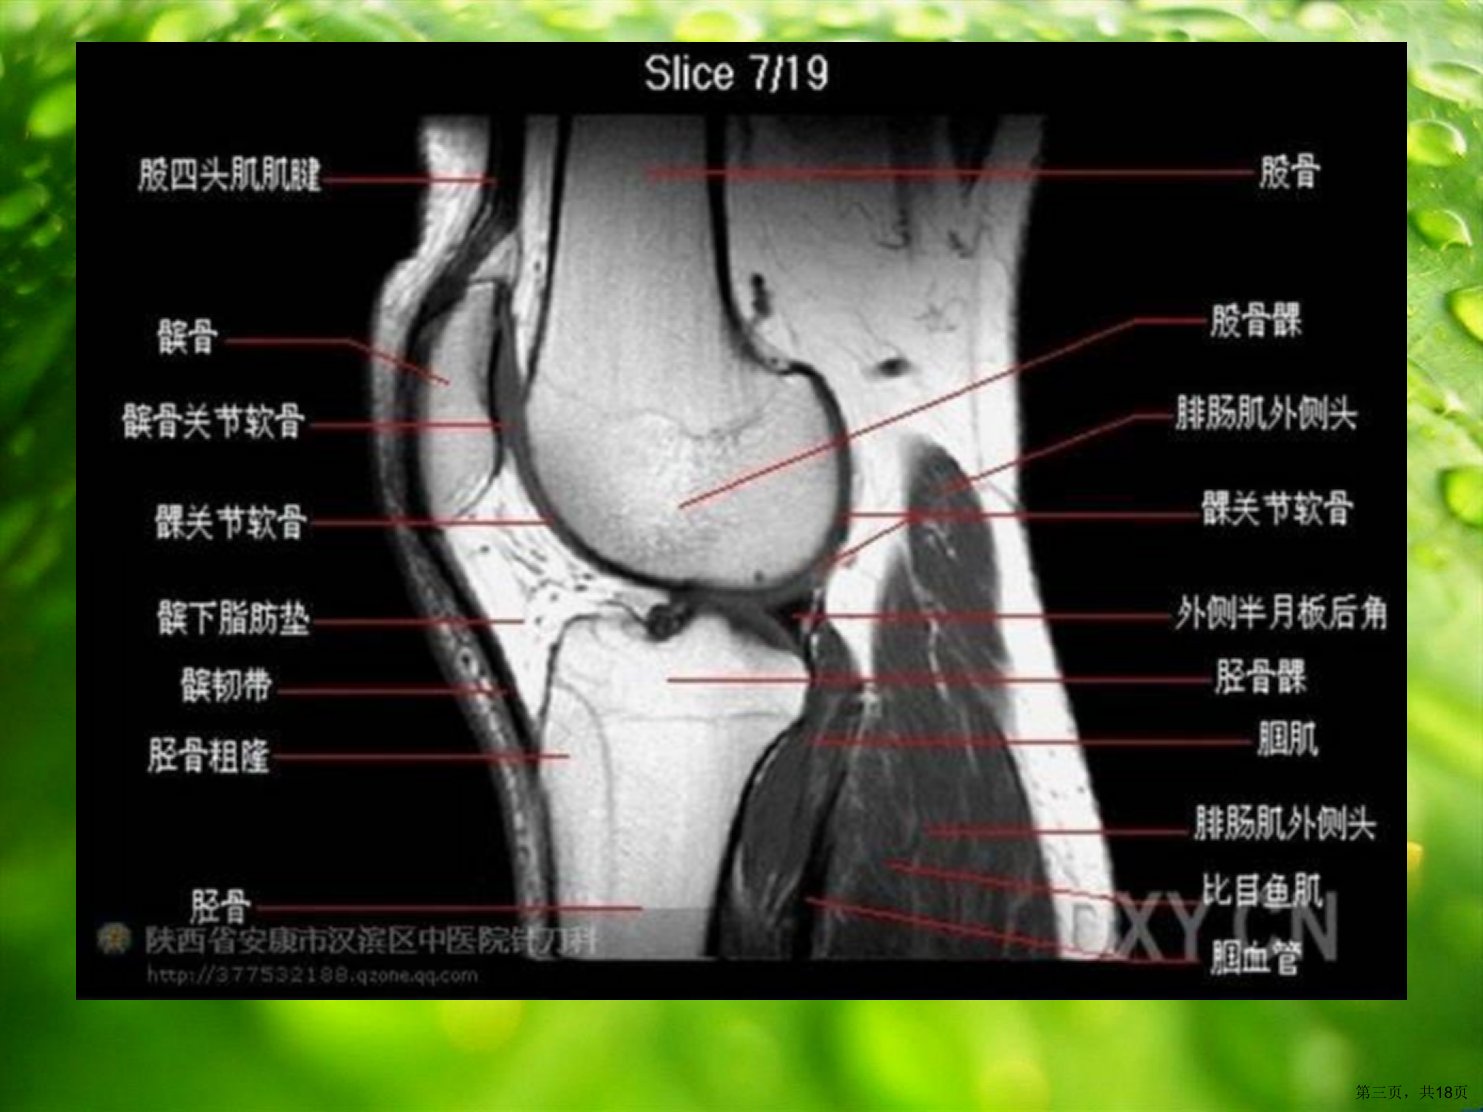

本文介绍了正常膝关节的超声检查方法。检查时需关注患者体位、关节位置和探头位置。膝关节按前外内后四个区域依次检查患者平卧必要时侧位或半侧位。扫查需长轴、短轴两个切面必要时双侧对比。检查时需熟悉肌肉肌腱解剖调整探头角度避免伪像。前侧结构主要关注股四头肌腱、髌腱和膑上囊检查膑上囊积液时探头勿加压。外侧区结构包括ITB、外侧副韧带和股二头肌腱以腓骨头为标志利于寻找。内侧结构主要是内侧副韧带、内侧半月板和鹅足腱二者损伤常合并存在检查时需结合横断面。后方结构检查时患者俯卧足略抬关注国动静脉、胫神经、坐骨神经和腓神经以及国窝囊肿发生地。